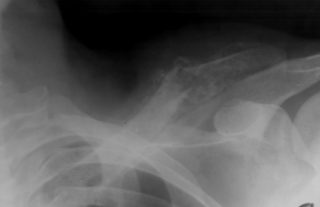

3. Травма акромиально-ключичного сустава

Травма сустава, соединяющего ключицу и лопатку, может вызывать боль и чувствительность

Акромиально-ключичный сустав находится в месте пересечения ключицы и лопатки.

Смещение сустава — распространённая травма, которая возникает в следствие приложения резкой силы или падения.

Травма акромиально-ключичного сустава может приводить к боли, но она не всегда сопровождается переломом или повреждением ключицы.

К другим симптомам данного состояния относятся:

- отёки;

- чувствительность;

- боль;

- смещение ключицы;

- выступ над плечом.

В зависимости от степени серьёзности травмы врач может порекомендовать следующее:

- обеспечение отдыха плечу и прикладывание холода;

- использование плечевой скобы для стабилизации сустава;

- операцию.